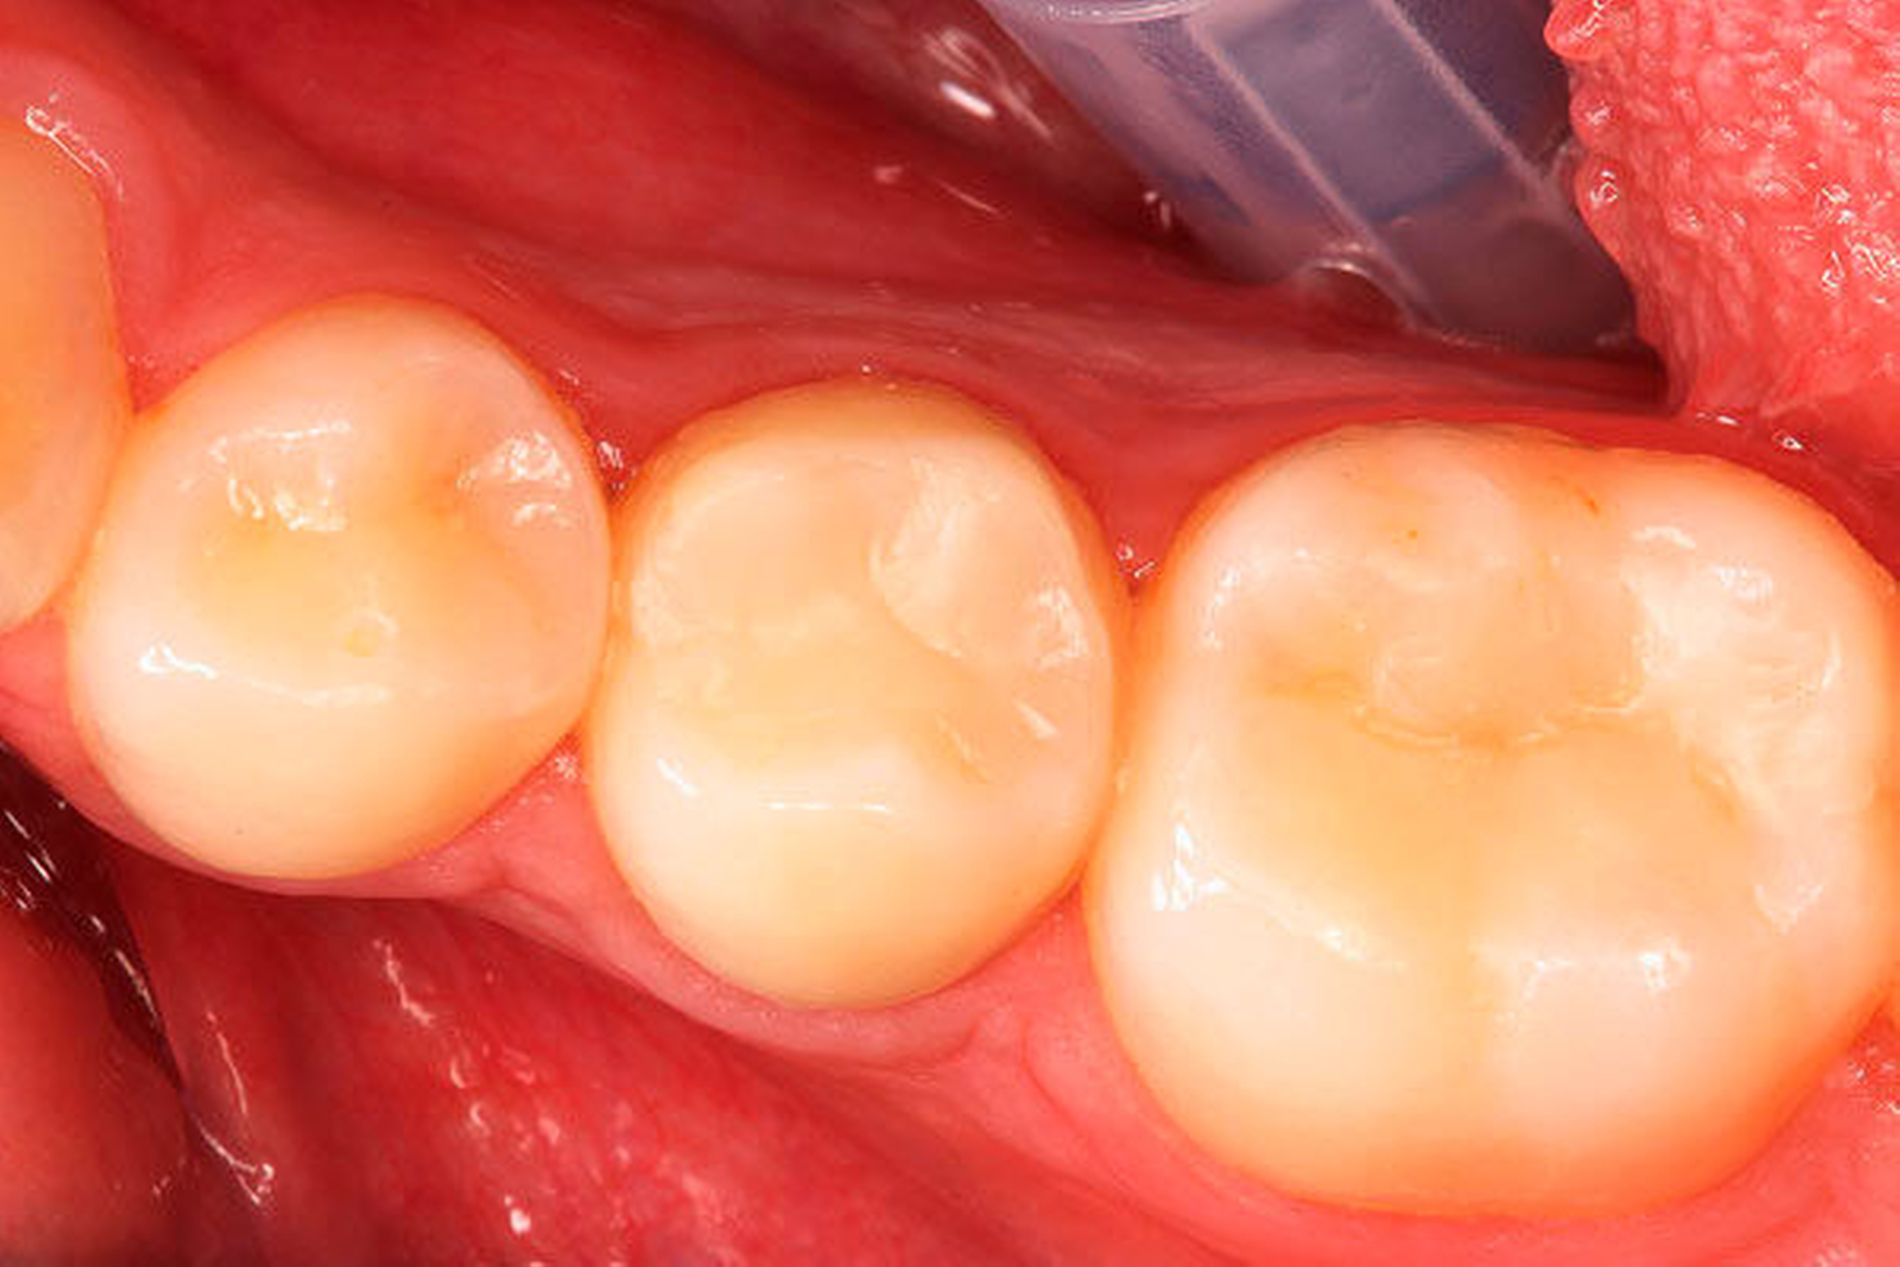

Klinisch stellte sich der Zahn als nicht perkussionsempfindlich dar und reagierte nicht auf den Kältetest. Es lag keine Schwellung vor, jedoch ein Fistelgang lingual des Zahnes 45 (Abbildung 2) sowie eine leichte Druckdolenz im Vestibulum Regio 45. Eine große Kavitation, wie es das Röntgenbild vermuten lässt, war klinisch nicht festzustellen (Abbildung 2). Die Nachbarzähne reagierten adäquat auf den Kältereiz und waren perkussionsunempfindlich. Die Fissurenversiegelung an Zahn 46 wurde als insuffizient bewertet.

Nach der Aufklärung von Patientin und Erziehungsberechtigten über die Therapiemöglichkeiten erfolgte in der ersten Behandlungssitzung die Kariesexkavation mit Kofferdam unter dem OP-Mikroskop mit Verzicht auf Lokalanästhesie. Nach vorsichtiger und schonender Entfernung der unterminierenden, tiefen Karies folgte zwangsläufig die großflächige Eröffnung des Pulpenkavums (Abbildungen 3 bis 6). Es folgte die Spülung mit Natriumhypochlorid-Lösung 5 % (NaOCl) und die Entfernung des nekrotischen Gewebes mittels Gates-Glidden-Bohrern der Größe 4 und 5 (ISO 110 und 130). Die Eröffnung der Pulpa sowie die Instrumentierung des Kanals spürte die Patientin nicht – bis zu einer Länge von 15 mm. Es erfolgte eine Einlage mit Ledermix-Paste (Riemser Pharma GmbH, Greifswald).